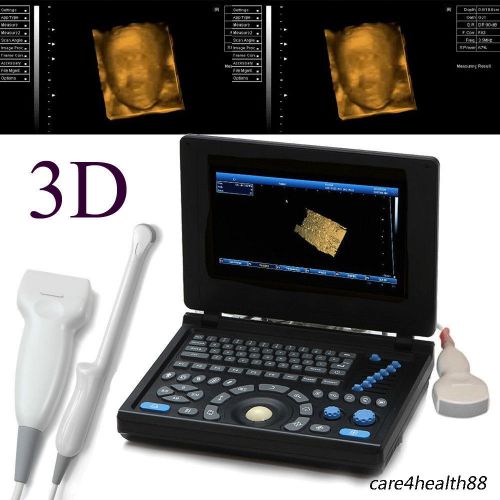

Model | RUS-9000E2 |

3D PC Full-digital Ultrasound scanner machine 3.5MHz Convex + Linear+ Tvaginal

3D PC Full-digital Ultrasound scanner machine 3.5MHz Convex +mirco-Convex probe

3D Full Digital Laptop Ultrasound Scanner (PC) With Convex probe & Transvaginal